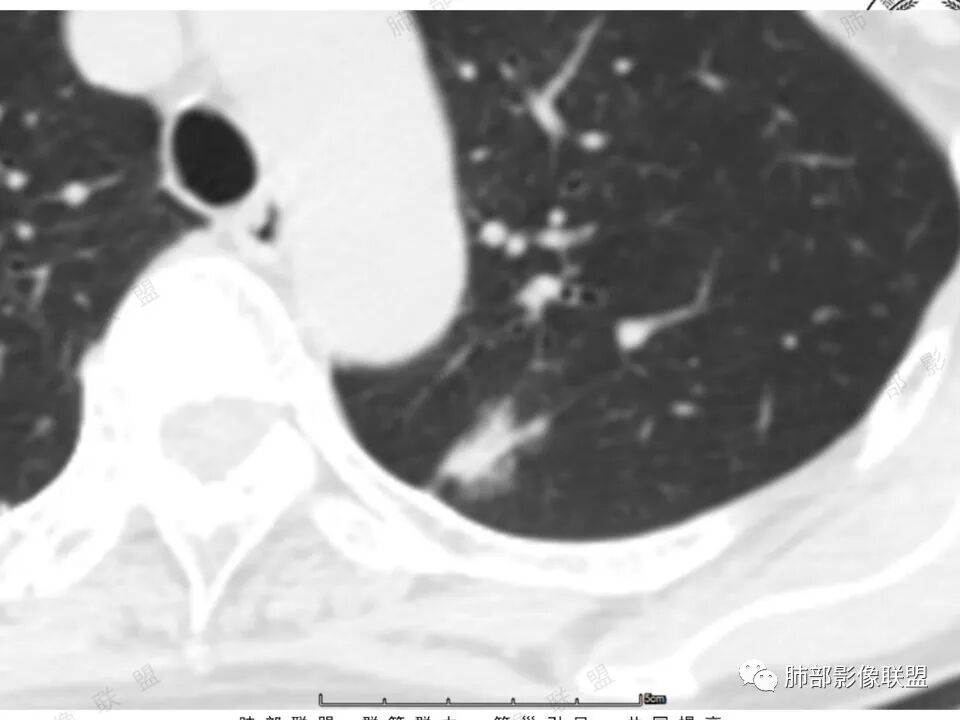

高强化,实性结节,边缘有磨玻璃,有膨隆,斜裂侧偏平直胸膜凹陷,IAC,鉴别炎性肉芽肿

左肺上叶长条状病灶,胸膜牵拉,边缘平直,磨玻璃边界清楚,不均匀强化,考虑炎性,不完全排除肺癌

左肺结节,形态不规则,边缘略收缩,分叶,部分边缘平直,周围可见清晰磨玻璃影,增强后明显强化,考虑:血管瘤,炎性假瘤,鉴别腺癌

左肺上叶尖后段病灶,毛玻璃边界不清,实性成分边缘平直,重建,病灶长条形,增强明显强化,考虑炎症

中年女,左肺结节,边缘平直,明显持续不均匀强化,周围略毛糙,考虑IMT

左肺结节,形态不规则,磨玻璃边界欠清,增强明显强化,考虑炎性,OP?IMT?,鉴别腺癌

中年女性,左肺上叶长条状病灶,宽基底与胸膜交界,胸膜凹陷,病灶边缘平直,局部收缩及膨隆,周围可见磨玻璃,其边界清楚,增强病灶不均匀强化,影像表现有炎性病变,也有明显占位表现,考虑OP,有膨胀性表现的小结节,不完全排除肺癌!需要结合相关检查。

混合磨玻璃,边界清,边缘凹陷,月牙铲,虽明显强化,还是先考虑腺癌,鉴别炎性肉芽肿或IMT等。

晨读:中年女性,体检发现,左肺上叶结节,形态不规则,呈长条状,分叶,部分边缘平直,周围可见磨玻璃影,增强后明显强化,首先考虑良性病变:1、炎性病变。2、血管瘤。

体检发现左肺上叶尖后段混合磨玻璃结节,考虑浸润性腺癌可能性大,建议抗感染后复查,明显强化有不支持的地方,左肺上叶尖后段外侧胸膜下小磨玻璃结节,提示AAH。

女,41岁,体检发现肺部结节。左肺上叶长形病灶,具有轻度膨胧感,刀切尖角征,胸膜粘连,早期强化见薄环强化征象,后期有延迟强化特点。病灶周围不是很干净。考虑结核肉芽肿或炎症肉芽肿。

中年女性,查体发现左上肺条块结节,靠近斜裂,边缘平直有收缩,胸膜牵拉,明显强化,考虑炎性假瘤或炎性肉芽肿,鉴别腺癌。

中年女性,体检发现。左肺上叶后段不规则结节灶,密度不均匀,病灶周围可以边界似清非清毛玻璃影,临近胸膜牵拉,增强扫描病灶明显不均匀强化。考虑炎性假瘤,鉴别腺癌。

混合磨玻璃,边界清,分叶,收缩力强,月牙铲,胸膜凹陷,虽明显强化,还是先考虑腺癌,鉴别炎性肉芽肿。

左肺上叶尖后段实性结节,边缘有清晰磨玻璃,胸膜有牵拉凹陷,明显强化,CT值超过主动脉,考虑血管畸形(周围磨玻璃可能是出血),鉴别IAC(影像表现符合,强化不符)

混合密度结节,磨玻璃密度边缘清楚,考虑腺癌。

患者中年女性,体检发现。胸部CT:左肺上叶后段长条形结节灶,边缘光滑,边界清楚,见分叶、毛刺、胸膜牵拉及平直征象。增强明显强化,内可见血管增粗,综合考虑恶性病变,浸润性腺癌可能大,鉴别结核。

形态特征符合腺癌,就是这个强化幅值相对少见些,肺内其他高强化病变如类癌、血管瘤等形态又不甚符合。还是常规考虑浸润腺癌吧,当然抗炎复查这个过程还是要的。

41岁女性,左肺上叶不规则结节,边缘见似清非清的磨玻璃影,叶间裂牵拉。整体病灶边缘平直,强化明显。另左上叶外侧尚有一磨玻璃结节(蘑菇兄弟?),考虑炎性肉芽肿可能性大。强化太明显让人很纠结,会不会存在CD,但边缘又有磨玻璃影;腺癌、结核、隐球都没有见过强化这么明显的,强化程度与主动脉基本一致,不会是动静脉畸形吧。

左上肺前后段不规则实性病灶,浅分叶,边缘部分平直收缩,轻微胸膜牵拉,伴周围磨玻璃样改变,强化明显,感觉是炎性恶性征像均有。

左肺上叶后段条片状影,边缘部分模糊,前缘平直后缘澎隆,周围可见大部分清晰的GGO,毛刺不明显,可见索条影,内密度不均可见条状低密度,增强除条状低密度外明显强化。支气管似见病灶边缘截断。考虑腺癌可能,抗炎治疗除外炎性肉芽肿。

强化太猛,血管畸形?边缘磨玻璃区,腺癌?